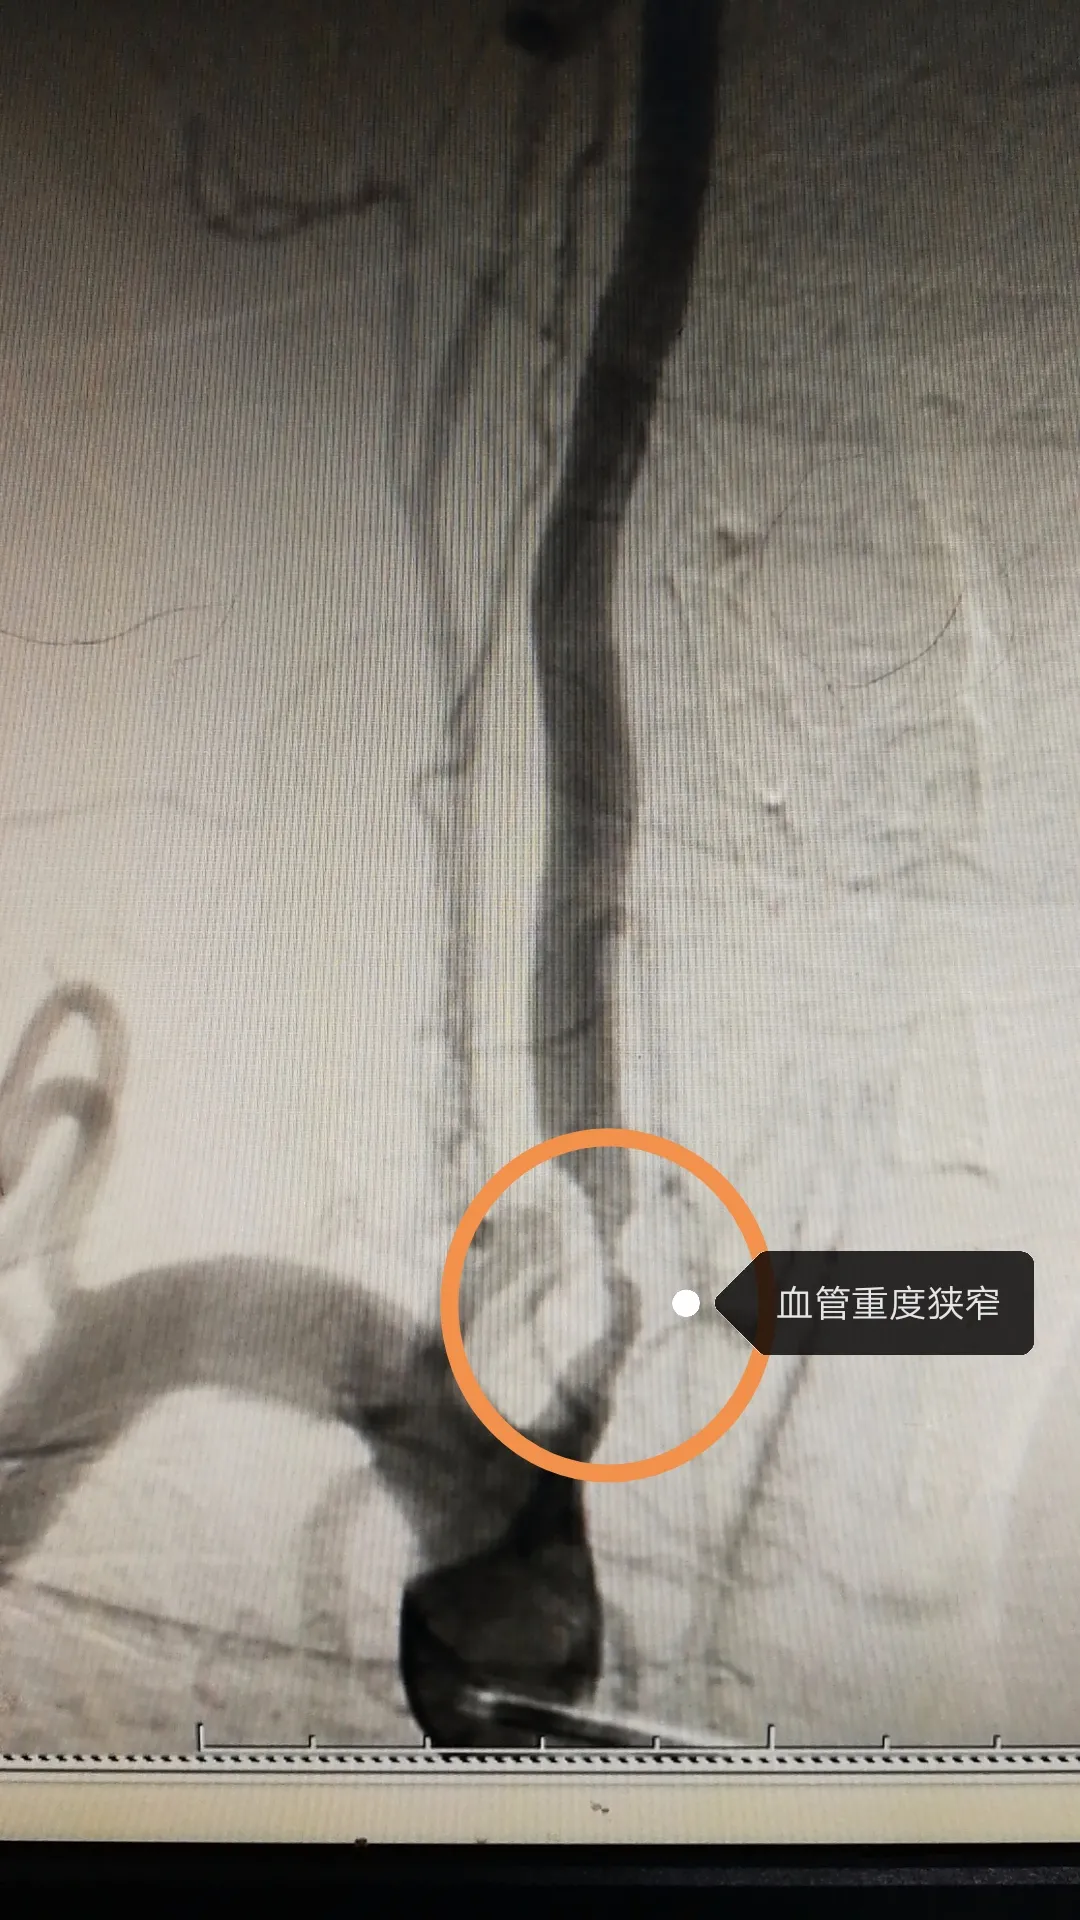

老人反复头晕近10年走路像在踩棉花竟是椎动脉重度狭窄惹的祸

左侧椎动脉起始处重度狭窄

行dsa检查发现其右侧椎动脉重度狭窄经诊断为椎基底动脉系统供血不足